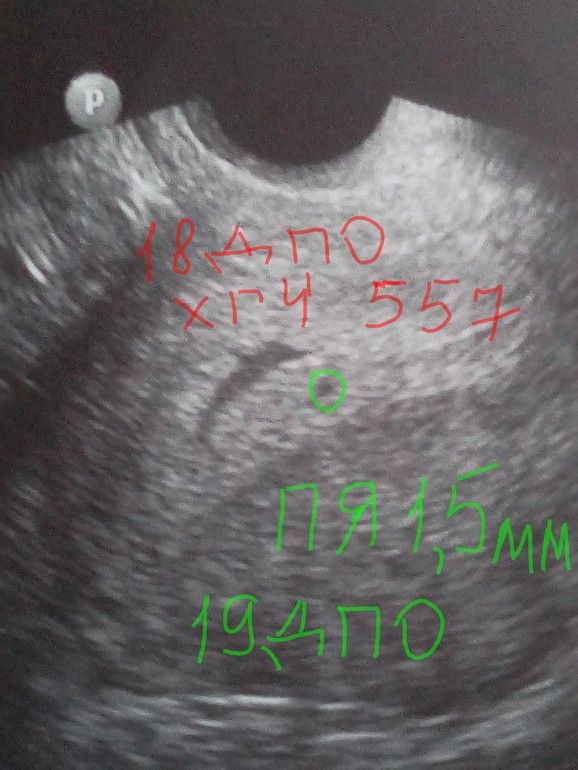

Изображение ХГЧ на 18 дпо был 557, на 19 дпо увидели ПЯ 1,5 мм, и то под вопросом на новейшем аппарате УЗИ. Позже повторите . Удачи🤞